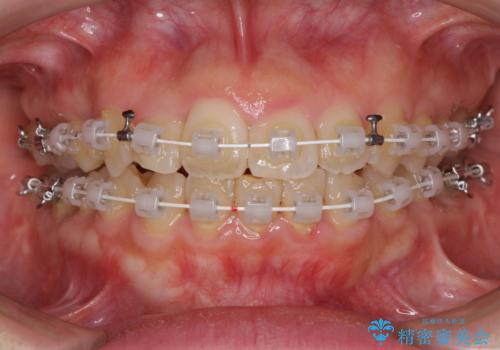

- 矯正装置

- 審美装置

- 右上の八重歯と、左下八重歯を抜いてしまったことを気にして来院された患者様です。

下顎は既に犬歯を1本抜歯しているため、上顎右側第一小臼歯を抜歯し、ワイヤー装置にて歯列を整えることとしました。

変則的な抜歯となるため、正中と人中がずれる可能性がありましたが、仕上がりは上下正中を揃えることができました。